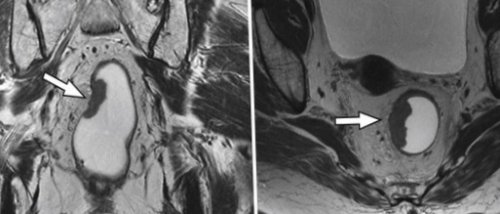

МРТ: рак прямой кишки клетчатку, мезоректальную фасцию, мочевой пузырь, семенные пузырьки, простату у мужчин, матку с шейкой

точно визуализирует инвазию

(стрелка), новообразование ограничено стенкой

у женщин. Поражение регионарных и